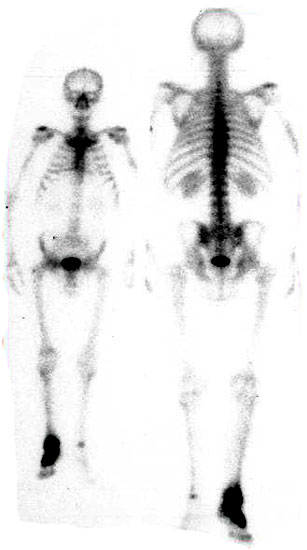

Abbildung 1

Während sich im CT  erst nach Wochen eine Osteopenie darstellen lässt, zeigt sich im Szintigramm bereits im frühen Stadium eine erhöhte Anreicherung des Radionuklids in der betroffenen Region (Abb. 6). Diese ist Folge der verstärkten Vaskularisation und des erhöhten Knochenumsatzes {ref: 15049532, 9462360, 16228105, 15045549}